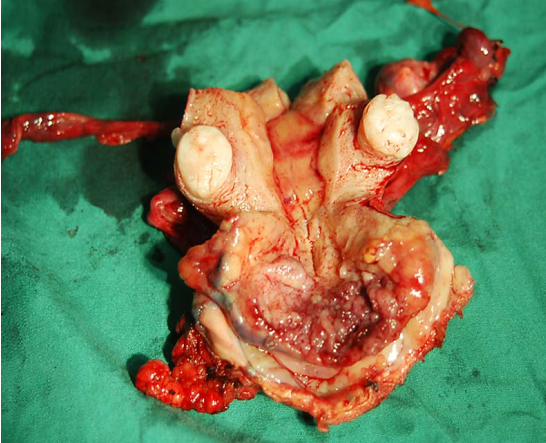

(1)巨检:微小浸润性鳞状细胞癌肉眼观察无明显异常,或类似子宫颈柱状上皮异位。随病变发展,可形成4种类型(图25-5)。

图25-5 子宫颈癌类型(巨检)

1)外生型:最常见,癌灶向外生长呈乳头状或菜花样,组织脆,触之易出血。常累及阴道。

2)内生型:癌灶向子宫颈深部组织浸润,子宫颈表面光滑或仅有柱状上皮异位,子宫颈肥大变硬,呈桶状。常累及宫旁组织。

3)溃疡型:上述两型癌组织继发展合并感染坏死,脱落后形成溃疡或空洞,似火山口状。

4)颈管型:癌灶发生于子宫颈管内,常侵人子宫颈管和子宫峡部供血层及转移至盆腔淋巴结。

内生型 外生型

溃疡型 颈管型

(1)巨检:来自子宫管内,浸润管壁;或自子宫颈管内向子宫颈外口突出生长;常可侵犯宫旁组织;病灶向子宫颈管内生长时,子宫颈外观可正常,但因子宫颈管膨大,形如桶状。

从左至右依次为Ⅰ、Ⅱ、Ⅲ及Ⅳ型子宫切除术的范围 Ⅰ型即筋膜外子宫切除术标本

Ⅲ型即广泛子宫切除术标本 盆腔淋巴结切除术标本

广泛子宫颈切除术切除的子宫颈及宫旁组织 广泛子宫颈切除术后功能重建的子宫及双附件